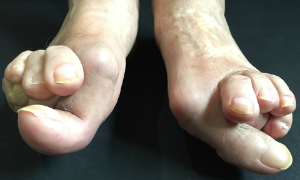

・ハンマートゥ

これらは外反母趾の方に見る外反母趾以外に抱える悩みや症状などです。